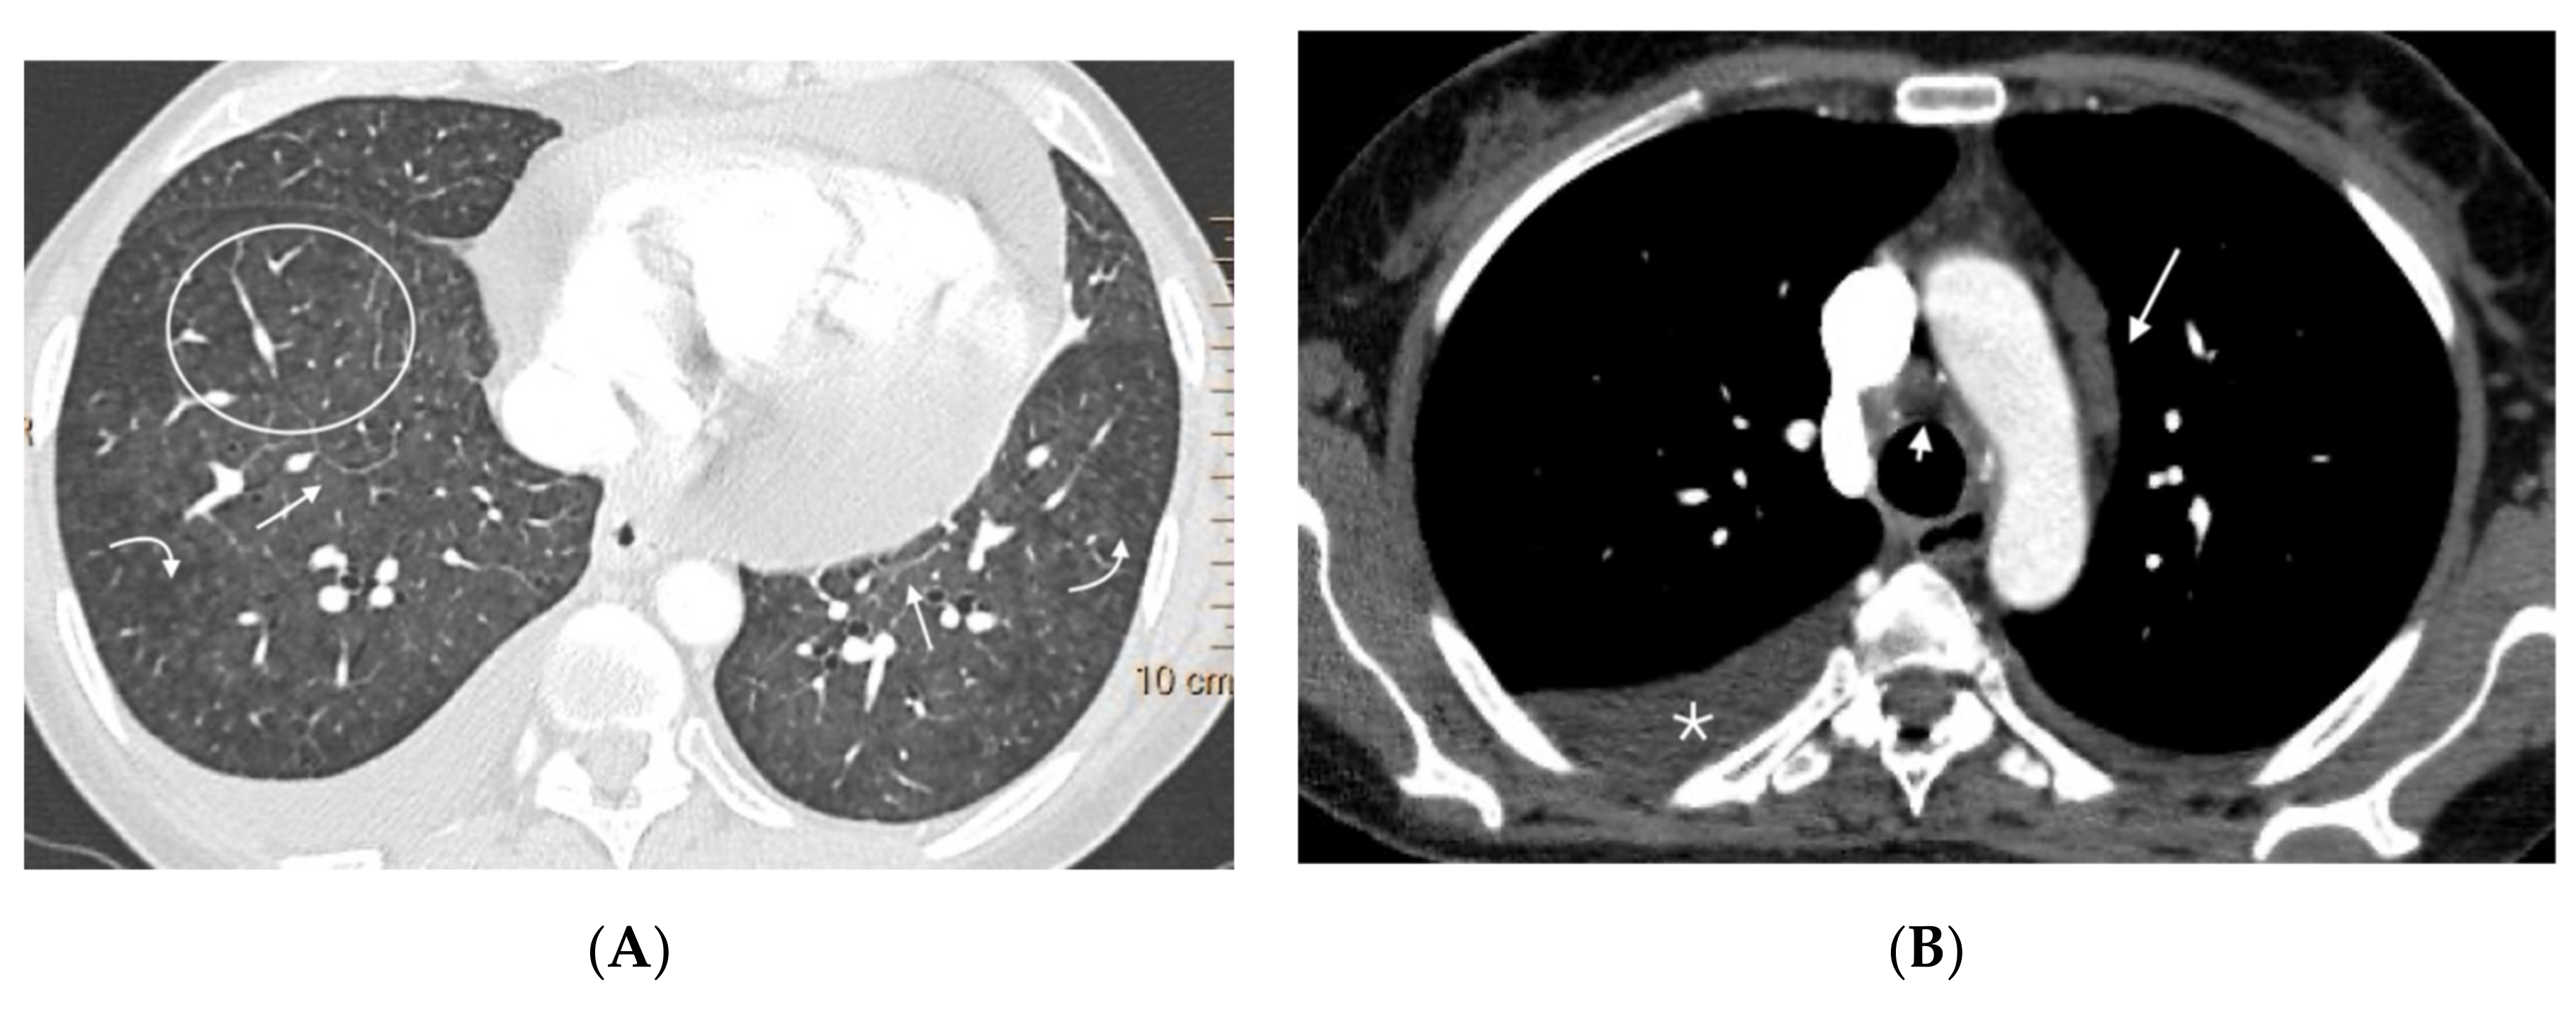

Figure 3.

Fifteen-year-old male with hereditary PVOD and three typical findings of PVOD in MDCT. Radiological signs of pulmonary hypertension: (A) Dilation of the pulmonary artery (PA) trunk and (B) Dilation of the right heart chambers with RV/LV ratio >0.9, hypertrophy of the right ventricular wall, and inversion of the interventricular septum; (C) Extensive involvement in centrilobular nodular ground glass (arrow) and septal lines (curved arrow). Mediastinal lymphadenopathy in subcarinal and bilateral hilar locations (arrows in (A)). PA: pulmonary artery. RA: right atrium. RV: right ventricle.